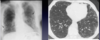

Identify types of pneumoconiosis and the compounds that initiate disease.

- What is notable about where asbestosis starts in the lungs?

- In asbestosis, contraction of the fibrous tissue distorts the normal architecture, creating enlarged air spaces enclosed within thick fibrous walls. What is the notable term used to describe the way the regions look?

- What is the most common manifestation of asbestos, and what are they made of /contain?

- What is shown in the image?

- How do patients with the asbestos present?

Identify types of pneumoconiosis and the compounds that initiate disease.

- What is notable about where asbestosis starts in the lungs?

- In contrast with CWP and silicosis, asbestosis begins in the lower lobes and subpleurally, spreading to the middle and upper lobes as the fibrosis progresses.

- In asbestosis, contraction of the fibrous tissue distorts the normal architecture, creating enlarged air spaces enclosed within thick fibrous walls. What is the notable term used to describe the way the regions look?

- Honeycombing

- What is the most common manifestation of asbestos, and what are they made of /contain?

- Pleural plaques are the most common manifestation of asbestos exposure and are well-circumscribed plaques of dense collagen, often containing calcium.

- They develop most frequently on the anterior and posterolateral aspects of the parietal pleura and over the domes of the diaphragm.

- What is shown in the image?

-

Asbestos bodies

- When asbestos fibers are inhaled, they become surrounded by alveolar macrophages and coated by a protein-iron complex, forming asbestos bodies.

- These bodies eventually undergo fibrosis, causing the lung tissue to become diffusely fibrotic and rigid and the airways to become distorted.

-

Asbestos bodies

- How do patients with the asbestos present?

- Progressively worsening dyspnea appears 10 to 20 years after exposure.

- It is usually accompanied by a cough and production of sputum.

- The disease may remain static or progress to CHF, cor pulmonale, and death.